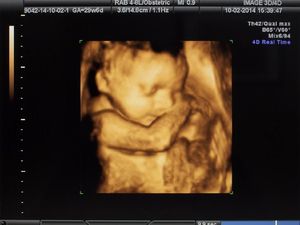

Intip Perkembangan Janin yang Menakjubkan di Trimester Dua

Ternyata, janin berkembang cukup pesat di trimester kedua, Bun. Bikin takjub deh kalau melihat pertumbuhan mata, rambut hingga gerakannya.